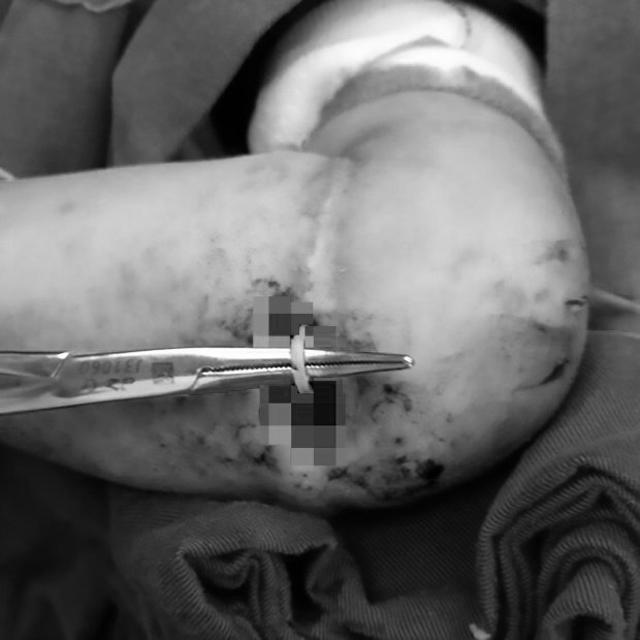

Các bác sĩ đã phẫu thuật và lấy ra chiếc dây thun bị "ăn sâu" vào cánh tay.

Rất may, Le Le đã được phẫu thuật kịp thời. Bé gái hiện vẫn nằm tại bệnh viện nhi và đang trên đà hồi phục.

Cánh tay của Le Le đang trên đà hồi phục và sẽ được tháo băng sớm.